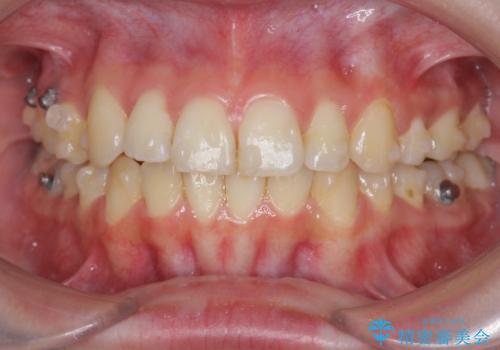

- 前歯の角度 奥歯の噛み合わせの改善をするために、矯正治療を希望され来院されました。

右側奥歯は上顎が相対的に前方に位置し(上顎前突)、そのため前歯の角度も突き出たようになり出っ歯のように見える状態でした。

マイクロインプラントを用いて、上顎奥歯を後方に移動させることで噛み合わせ・前歯の角度を改善していきます。

少し時間はかかりましたが、しっかりと綺麗な歯並びに仕上げることができ、大変喜んでいただくことができました。